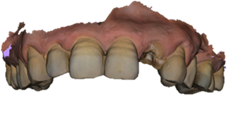

After scaling and root planing with hygiene motivation, we took a bimaxillary digital impression of the patient (Figure 3) and planned a tooth-supported surgical guide based on the complementarity between the STL file from the digital impression and the DICOM file from the CBCT (Figure 4, Figure 5).

Figure 4. Modeling the provisional prosthesis and selecting the implant axis